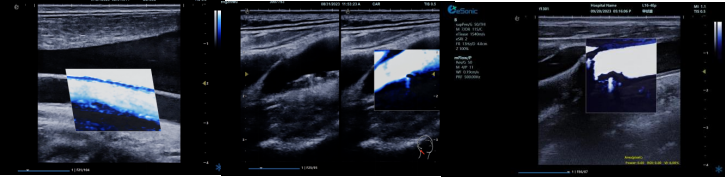

RawVisionTM Plaque技术(RVP

RVP 是世界领先的颈动脉斑块自动定量分析成像模式,依托 RawVisionTM原数平台强大的原始射频数据采集与分析能力。其优势显著:

? 可视化呈现方面,能分析斑块在特定条件下内部纹理变化,生成可视化参数成像。医生可依据颜色辨别易损与稳定斑块,并进行定量测量。

image.png

? 定量评估上,提供 CNTENTNRTCPT 等指标和参数,为监测老年颈动脉斑块风险提供客观准确依据。

? 借助 AI 自动分析,可快速筛选诊断,提升脑卒中筛查效率,有望重塑易损斑块临床诊断流程。

? 具备技术升级潜力,支持高端科研,能挖掘更多诊断参数,满足临床需求。

相比传统超声弹性成像技术,RVP 利用颈动脉搏动采集数据,避免了操作者施压等主观因素干扰,数据处理更精准,结果重复性佳,不受操作者差异影响。